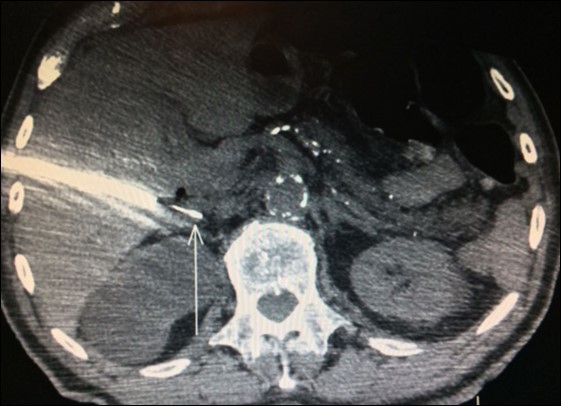

Nevertheless, in another study, only 28 out of 39 (71.8%) patients who underwent adrenalectomy for suspect adrenal tumor by FDG-PET/CT confirmed metastasis. Ten of those were benign adenoma and one was a non-functional pheochromocytoma29. Thus, FDG-PET/CT produced an unexpected high rate (28.2%) of false-positive results in this trial. Despite benign adenoma may mimicking metastasis and produce a positive preoperative FDG-PET/CT, history of primary lung malignancy and SUV max >2.65 were more commonly associated with metastasis in this paper (Figure 2).

Figure 2.PET-CT with high uptake on right adrenal

PET-CT with high uptake on right adrenal

PET-CT results for adrenal glands increases the likelihood of malignancy, but may only be considered indicative, not certainty of malignancy.